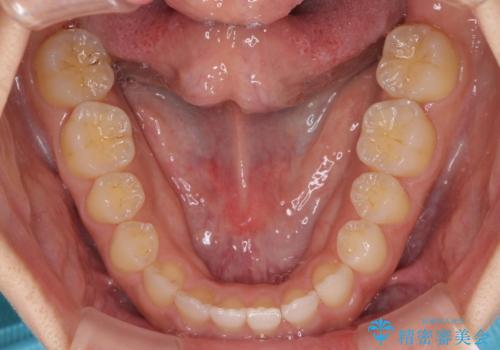

- 後戻りによる上下前歯の隙間を気にして来院された患者様です。

歯列不正はそれほど大きくなかったため、インビザライン・ライトを用いて矯正治療を行うこととしました。

無理のないペースで治療を進め、9ヶ月で終えることができました。